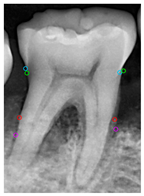

The prediction results of the three masks (Tooth, Bone, and Crown) using the aforementioned steps are shown in Figure 12, with different AP metrics evaluated using Equation (8). Table 9 presents the training results of Mask R-CNN for extracting these masks from original and enhanced images, assessed through AP, AP50, and AP75 metrics. For the Tooth Mask, image enhancement improved the AP from 66.73% to 69.65%, AP50 from 88.32% to 89.54%, and AP75 from 74.65% to 81.66%. For the Bone Mask, the AP increased from 73.32% to 76.66%, AP50 from 98.15% to 99.86%, and AP75 from 90.17% to 92.26%. For the Crown Mask, the AP improved from 79.14% to 81.55%, AP50 remained at 99.99%, and AP75 slightly decreased from 98.02% to 96.29%. These results indicate that whether using the bounding box or segmentation evaluation methods, the training outcomes for all three masks improved after image enhancement. This demonstrates the significant effectiveness of image enhancement techniques in increasing the detection accuracy of the Mask R-CNN model. The training process is shown in Table 10. The accuracy of Faster R-CNN for bounding box prediction and Mask R-CNN for mask segmentation prediction has significantly increased to more than 95% during the training process.

Figure 12.

Mask R-CNN prediction result: (a) single tooth (CLAHE), (b) Tooth Mask, (c) Bone Mask, and (d) Crown Mask.